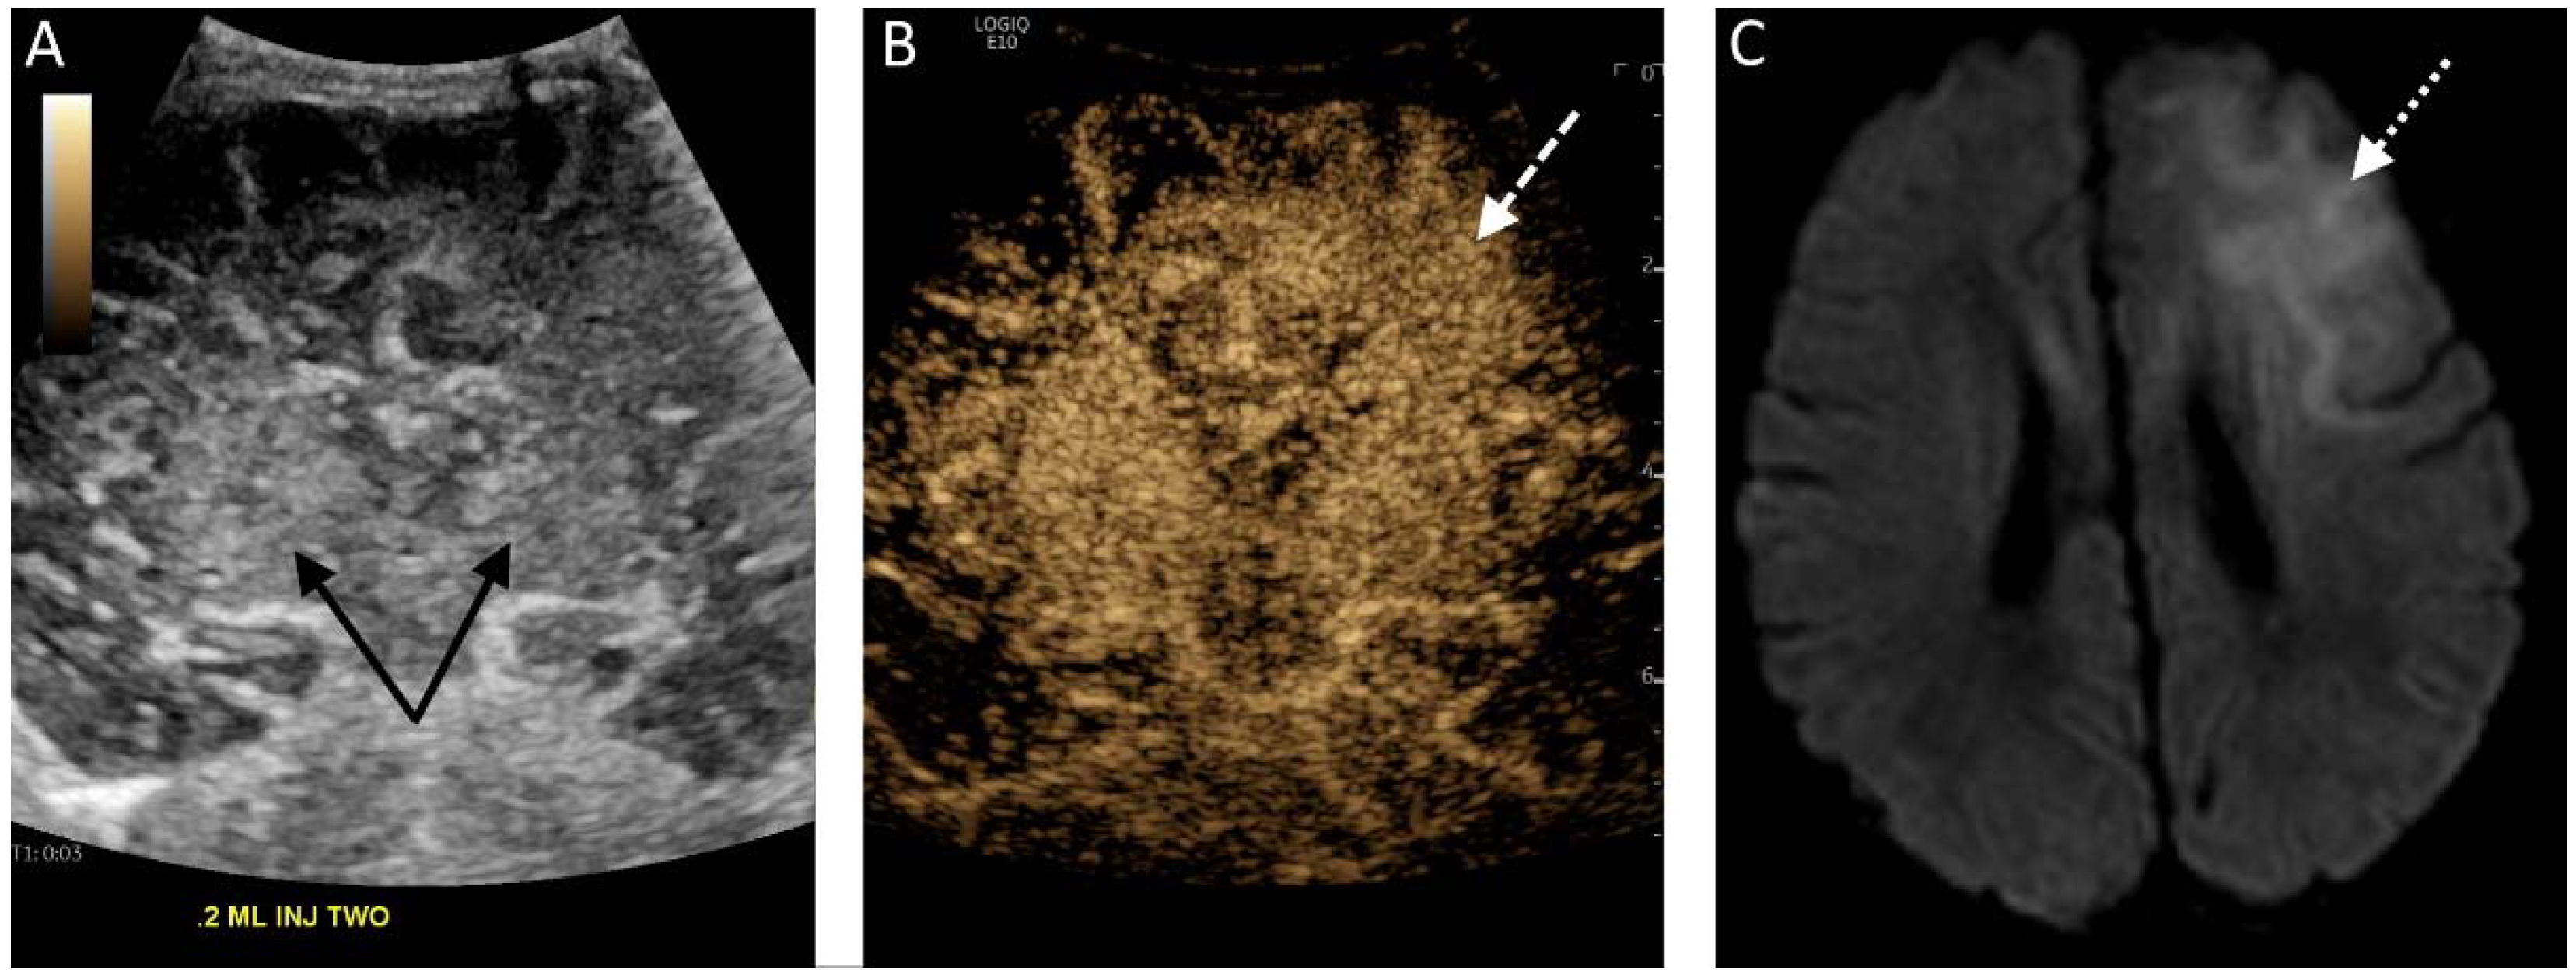

Figure 1.

(A) Midcoronal grayscale ultrasound image of a 2 day old newborn’s brain through the deep gray nuclei (black solid arrows). (B) The contrast-enhanced image acquired 5 s after a second bolus injection in the same plane demonstrates enhancement of the bilateral deep gray nuclei but also asymmetric hyperenhancement of the left frontal lobe (white dashed arrow), representing luxury perfusion in an area of infarct. (C) A diffusion-weighted MRI sequence confirms the presence of diffusion restriction in the left frontal lobe (white dotted arrow) consistent with left frontal infarct.